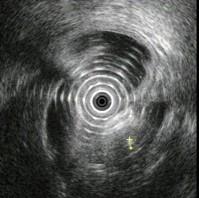

问题 图中胰腺病变可能的诊断是 ( )

选项 A.正常 B.胰腺囊肿 C.慢性胰腺炎 D.胰腺囊腺癌 E.胆总管结石

答案 C